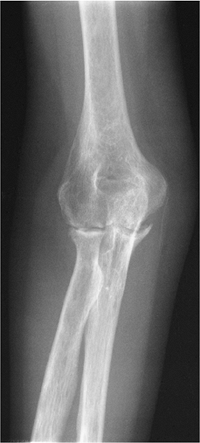

Fractures/Dislocations: Epicondylar Fractures

Key Facts

Avulsion fractures of the epicondyle are common in children.

The injury is common in throwing athletes, specifically pitchers.

The medial epicondyle is particularly vulnerable between ages 9 and 14 years.

Mechanism of injury is varus and valgus forces. Medial epicondylar fractures are common; lateral epicondylar fractures are rare.

Displaced medial epicondylar fragments may be trapped in the joint.

Routine radiographs usually are adequate

for diagnosis. MRI is useful for subtle undisplaced fractures and

associated soft tissue injuries. -

Treatment: closed reduction for undisplaced fractures; pinning of displaced (>3 mm) fractures.

Complications: fragment entrapped in joint, instability.

![]() |

FIGURE 8-3 AP radiograph of the elbow in a young pitcher with an avulsed medial epicondyle (arrow).